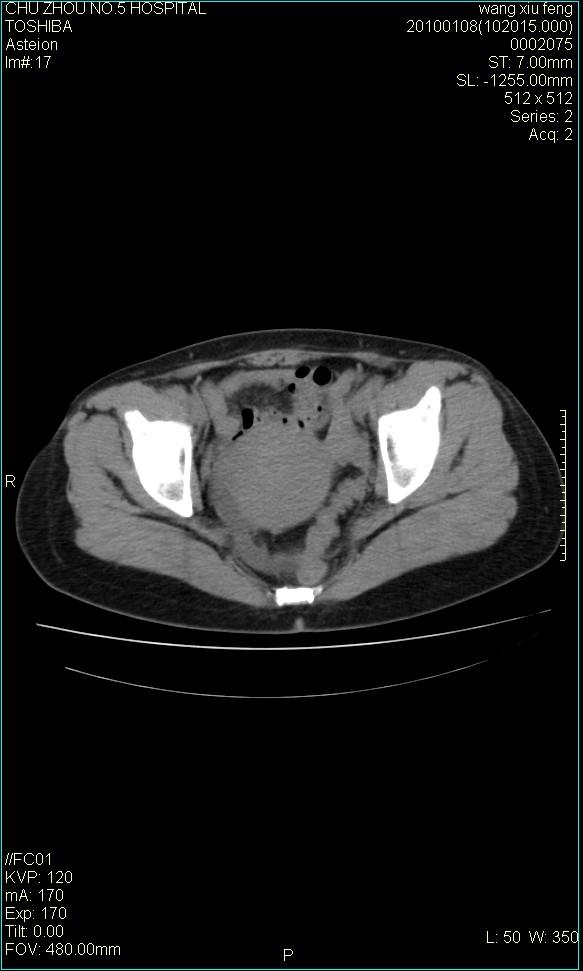

f-41,左乳腺ca术后4年,b超示:子宫右上方囊性包块约5.5*3.4cm,前日行胸部ct平扫未见明显异常。

考虑右侧卵巢囊腺瘤?

右侧卵巢囊肿或小囊腺瘤。

考虑右侧卵巢囊腺瘤。

考虑右侧卵巢囊性占位性病变(囊肿?囊腺瘤?)。